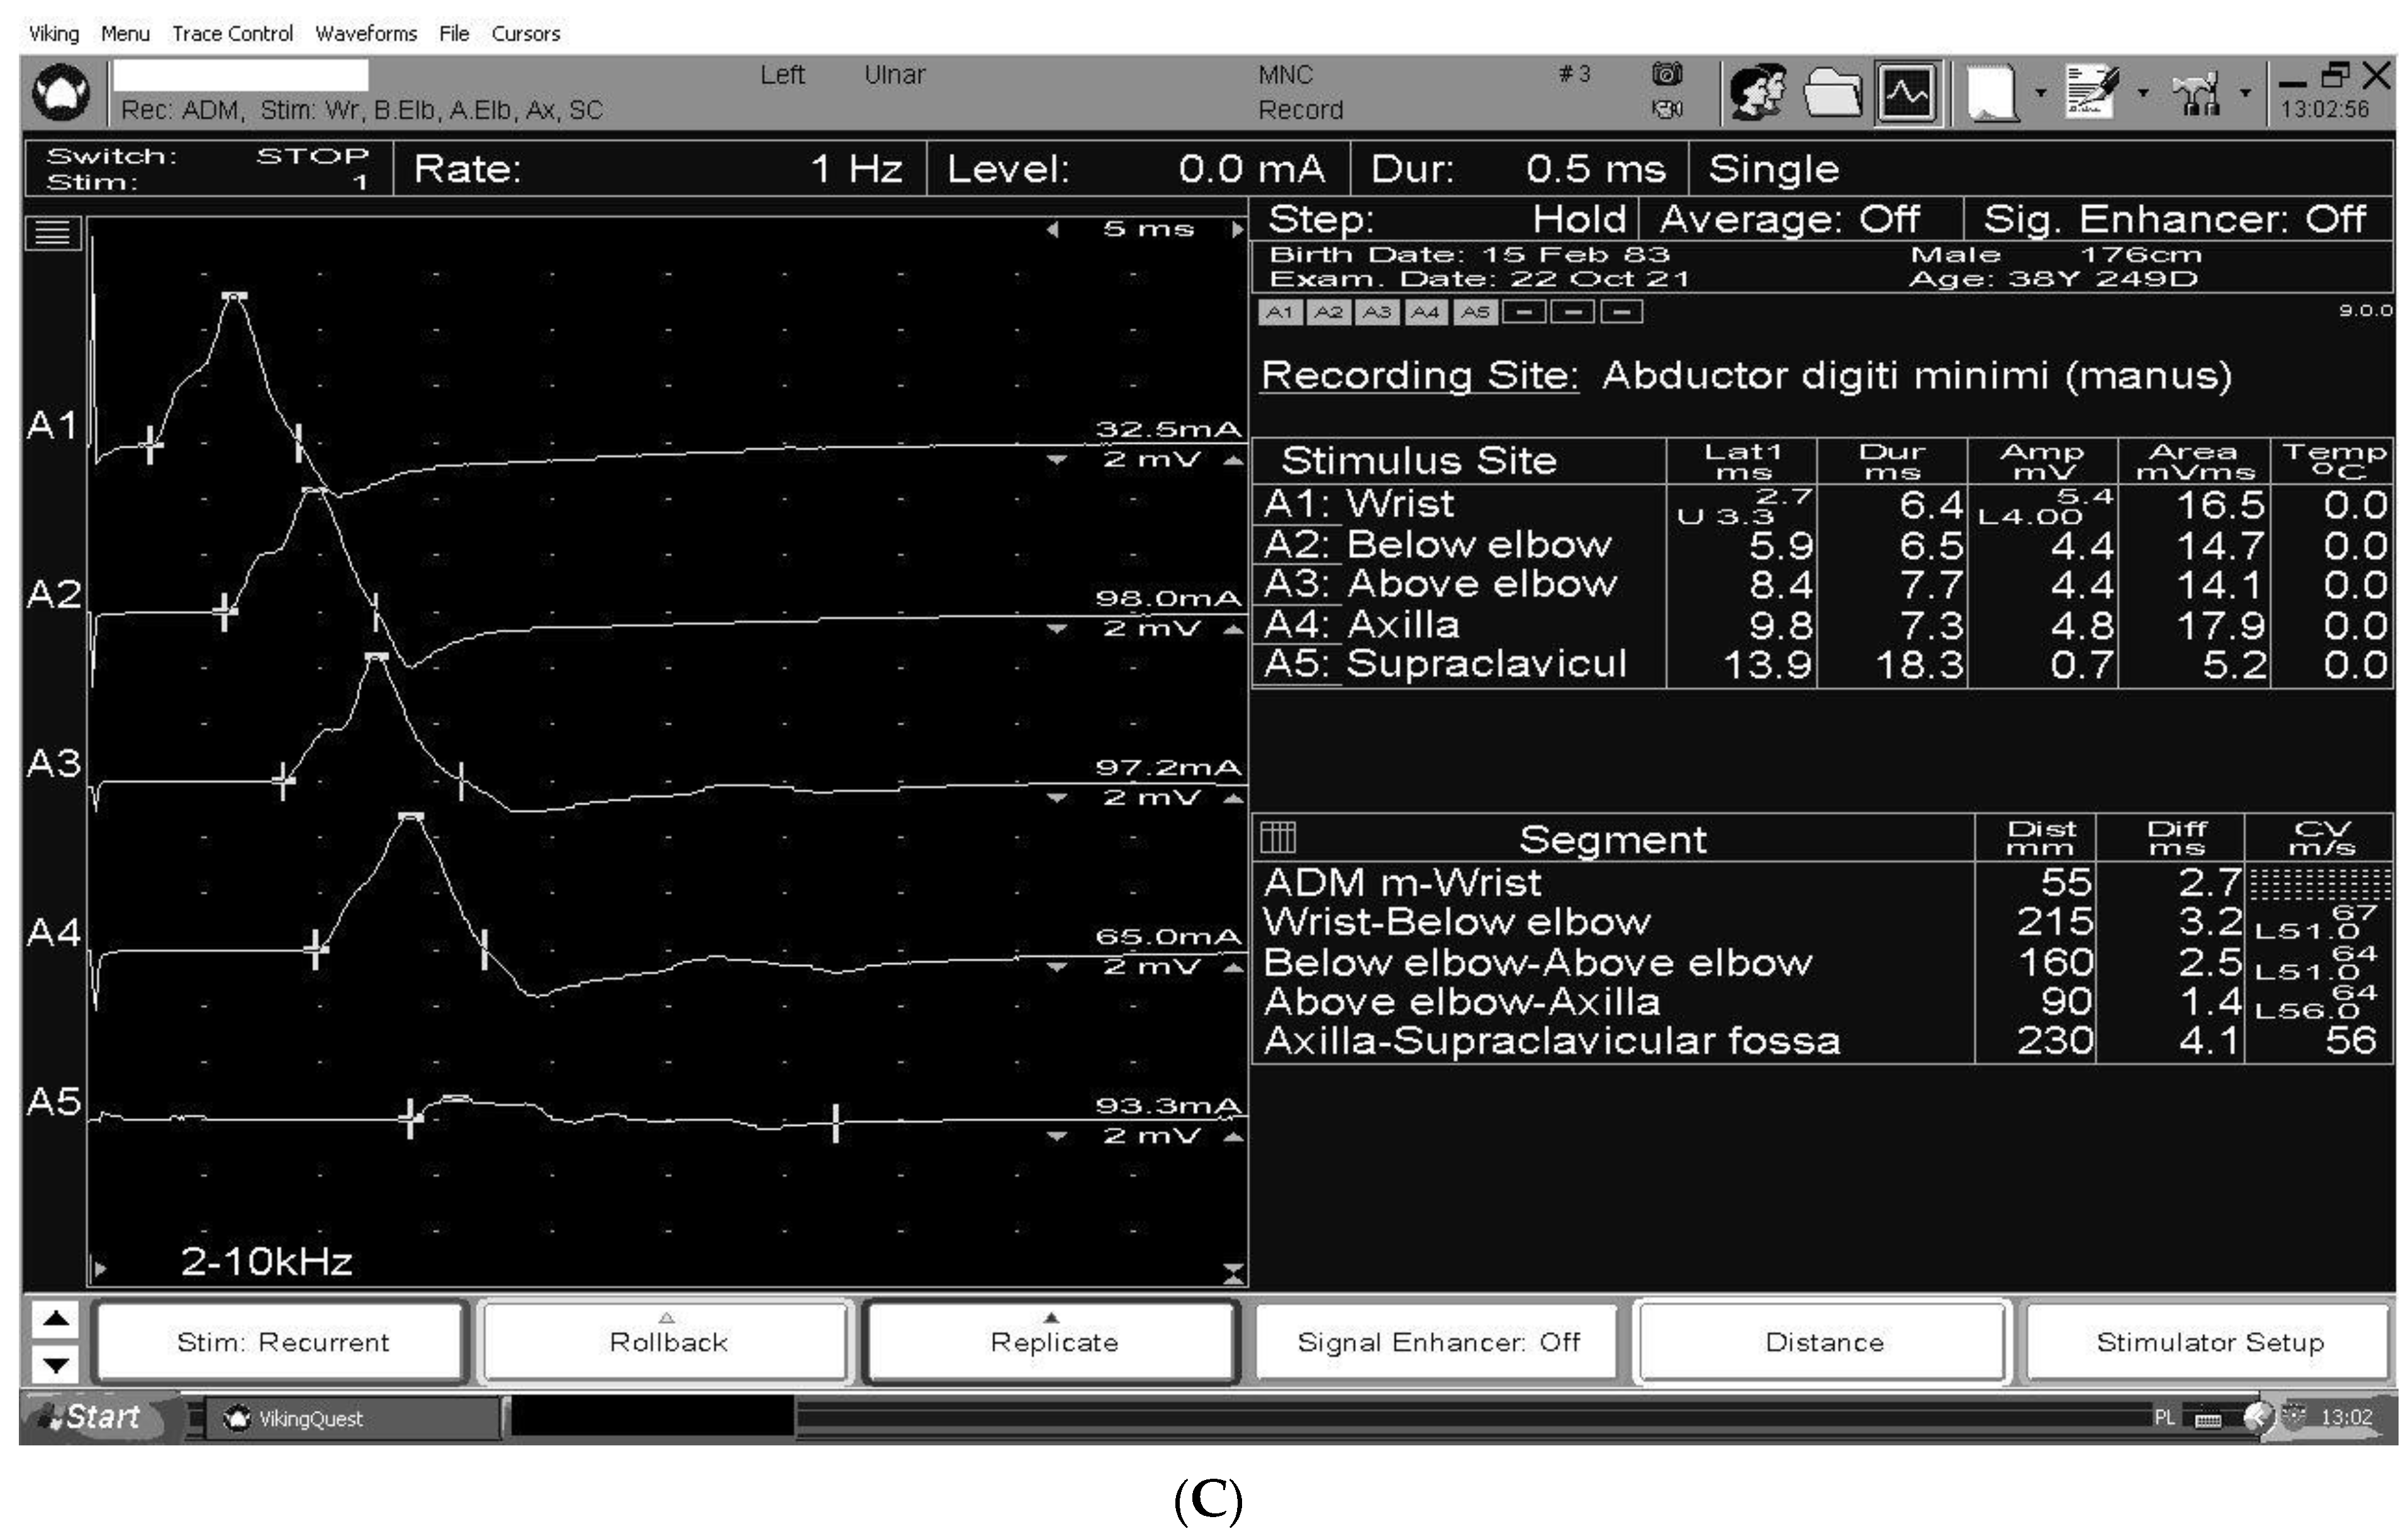

3. The Electrodiagnosis